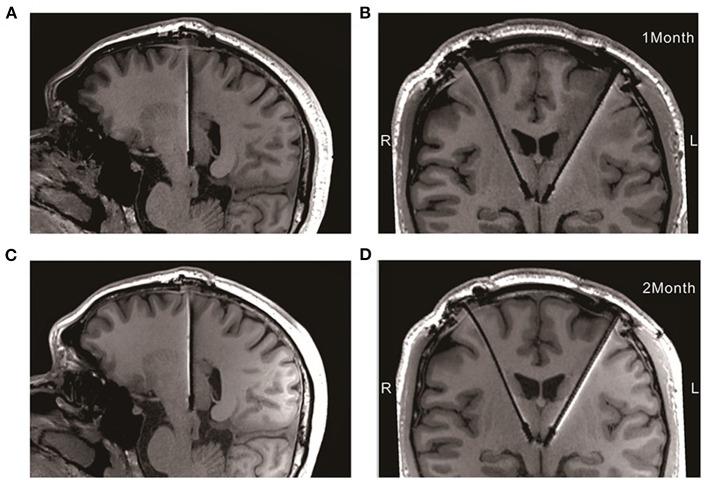

难治性抑郁症(TRD)是一种慢性重症精神疾病,治疗选择有限。深部脑刺激(DBS)是一种有望用于TRD患者的治疗方法。然而,其安全性和有效性仍不明确。在此,我们报告了外侧缰核(LHb)DBS对一名药物、心理、电休克及氯胺酮治疗均无效的TRD患者的安全性和有效性。该DBS系统与3T磁共振成像以及局部场电位(LFP)流兼容。两个DBS电极植入双侧LHb,未出现任何并发症。患者在左侧LHb 160 Hz频率刺激下表现出急性刺激效果,并在抑郁、焦虑和睡眠方面实现了长期改善,同时伴有LFP的变化。这些结果为LHb DBS治疗TRD的安全性、有效性及电生理基础提供了临床证据。

Treatment-resistant depression (TRD) is a chronic and severe psychiatric illness associated with limited therapeutic options. Deep brain stimulation (DBS) is a promising therapy for TRD patients. However, its safety and efficacy are still unclear. Here we reported the safety and efficacy of lateral habenula (LHb) DBS for a TRD patient who had failed medical, psychological, electroconvulsive, and ketamine therapy. The DBS system is compatible with 3T magnetic resonance imaging along with local field potential (LFP) streaming. Two DBS electrodes were implanted at the bilateral LHb without any complication. The patient showed acute stimulation effects and achieved long-term improvements in his depression, anxiety, and sleep with left LHb 160 Hz frequency stimulation, accompanying the change of LFPs. These results provided clinical evidence toward the safety and efficacy and electrophysiological basis of LHb DBS for TRD.